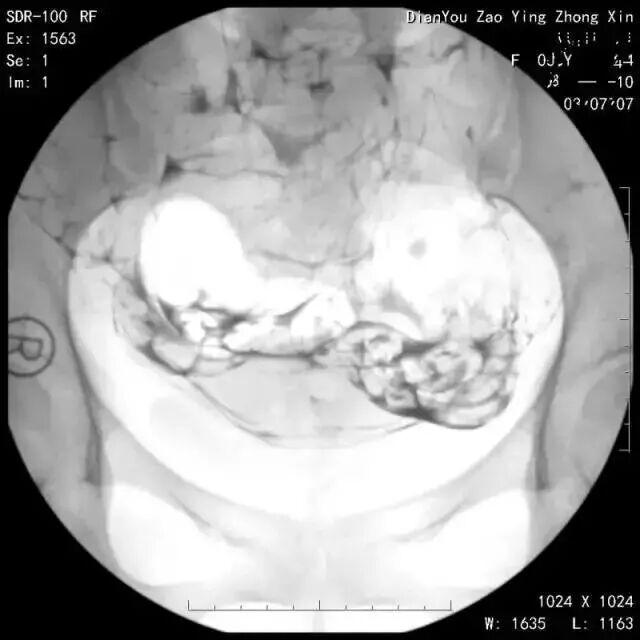

↓下图是输卵管积水的延迟片:

延迟涂抹片对于最后确诊输卵管的状态非常重要,如果没有,会影响输卵管诊断的准确性!

但是在以下情况中试管婴儿常常失败。这位女性因不孕症准备做试管婴儿,医生为她做了子宫输卵管造影,发现她的双侧输卵管远端非常扩张,这是什么问题?

原来这叫输卵管积水,慢性炎症是导致输卵管积水的原因。这种情况下,输卵管内的积水会流回宫腔,破坏宫腔怀孕的环境,试管婴儿失败!怎么办?